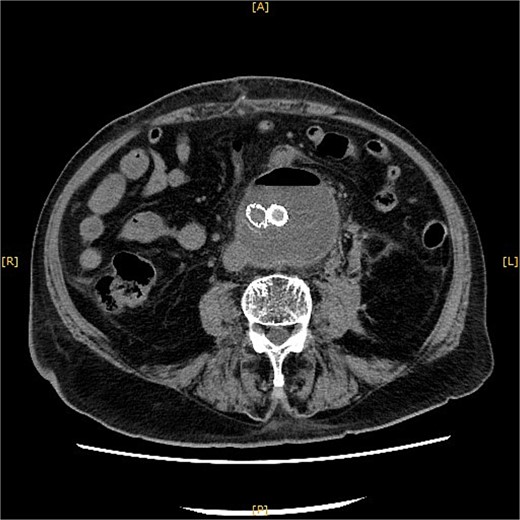

Contrast-enhanced CT revealed an AAA measuring 118 × 107 mm and left retroperitoneal hematoma. One pair of lumbar arteries was enhanced only in the delayed phase (red arrows). Intraoperatively, pulsatile bleeding was observed from the left one of this pair.

This time, he was brought to the emergency department with a chief complaint of abdominal pain. His medical history includes Stage 4–5 chronic kidney disease (CKD), with an estimated glomerular filtration rate (eGFR) of approximately 15 mL/min/1.73 m2, secondary to nephrosclerosis and diabetic nephropathy, as well as persistent atrial fibrillation, which was treated with warfarin. Upon admission, laboratory results revealed a hemoglobin level of 6.2 g/dl and a prothrombin time—international normalized ratio (PT-INR) of 6.05. Contrast-enhanced CT demonstrated an AAA measuring 118 × 107 mm, enlarged from 98 × 94 mm 2 months prior, and left retroperitoneal hematoma. IMA and one pair of lumbar arteries were enhanced only in the delayed phase, but blood flow into the aneurysm was not clearly observed (Fig. 1). Given that the landing zones and overlaps of the stent grafts were satisfactory (Fig. 2) and that no type I or type III endoleaks were identified, a ruptured AAA due to TIIEL from the lumbar artery or IMA was highly suspected. We administered 3000 IU/kg of lyophilized human prothrombin complex concentrate in response to the significant prolongation of PT-INR and proceeded with open surgery for ligation of the feeding artery and aneurysmorrhaphy. Intraoperatively, no pulsation was found on the aneurysm. Incision of the aneurysm revealed a large amount of thrombus, which was removed, and then pulsatile bleeding was identified from a lumbar artery (Fig. 3), the ostium of which was sutured from within the aneurysm. This was consistent with the left lumbar artery of the pair enhanced on the preoperative CT and was suspected to be responsible for the rupture. Oozing was also noted from several other lumbar arteries, which were similarly sutured closed. No leak was observed from the proximal or distal ends, nor from the junctions of the stent grafts, and no damage to the stent grafts was observed (Fig. 4). Following this, aneurysmorrhaphy was performed, and the abdomen was closed. The postoperative course was uneventful. A plain CT on postoperative day (POD) 14 showed a reduction in the aneurysm size with no apparent leaks (Fig. 5). The patient was discharged home on POD 24. Although the preoperative eGFR was 8.8 ml/min/1.73 m2, no postoperative deterioration was observed. It gradually improved back to baseline, and dialysis was not required during the follow-up period.